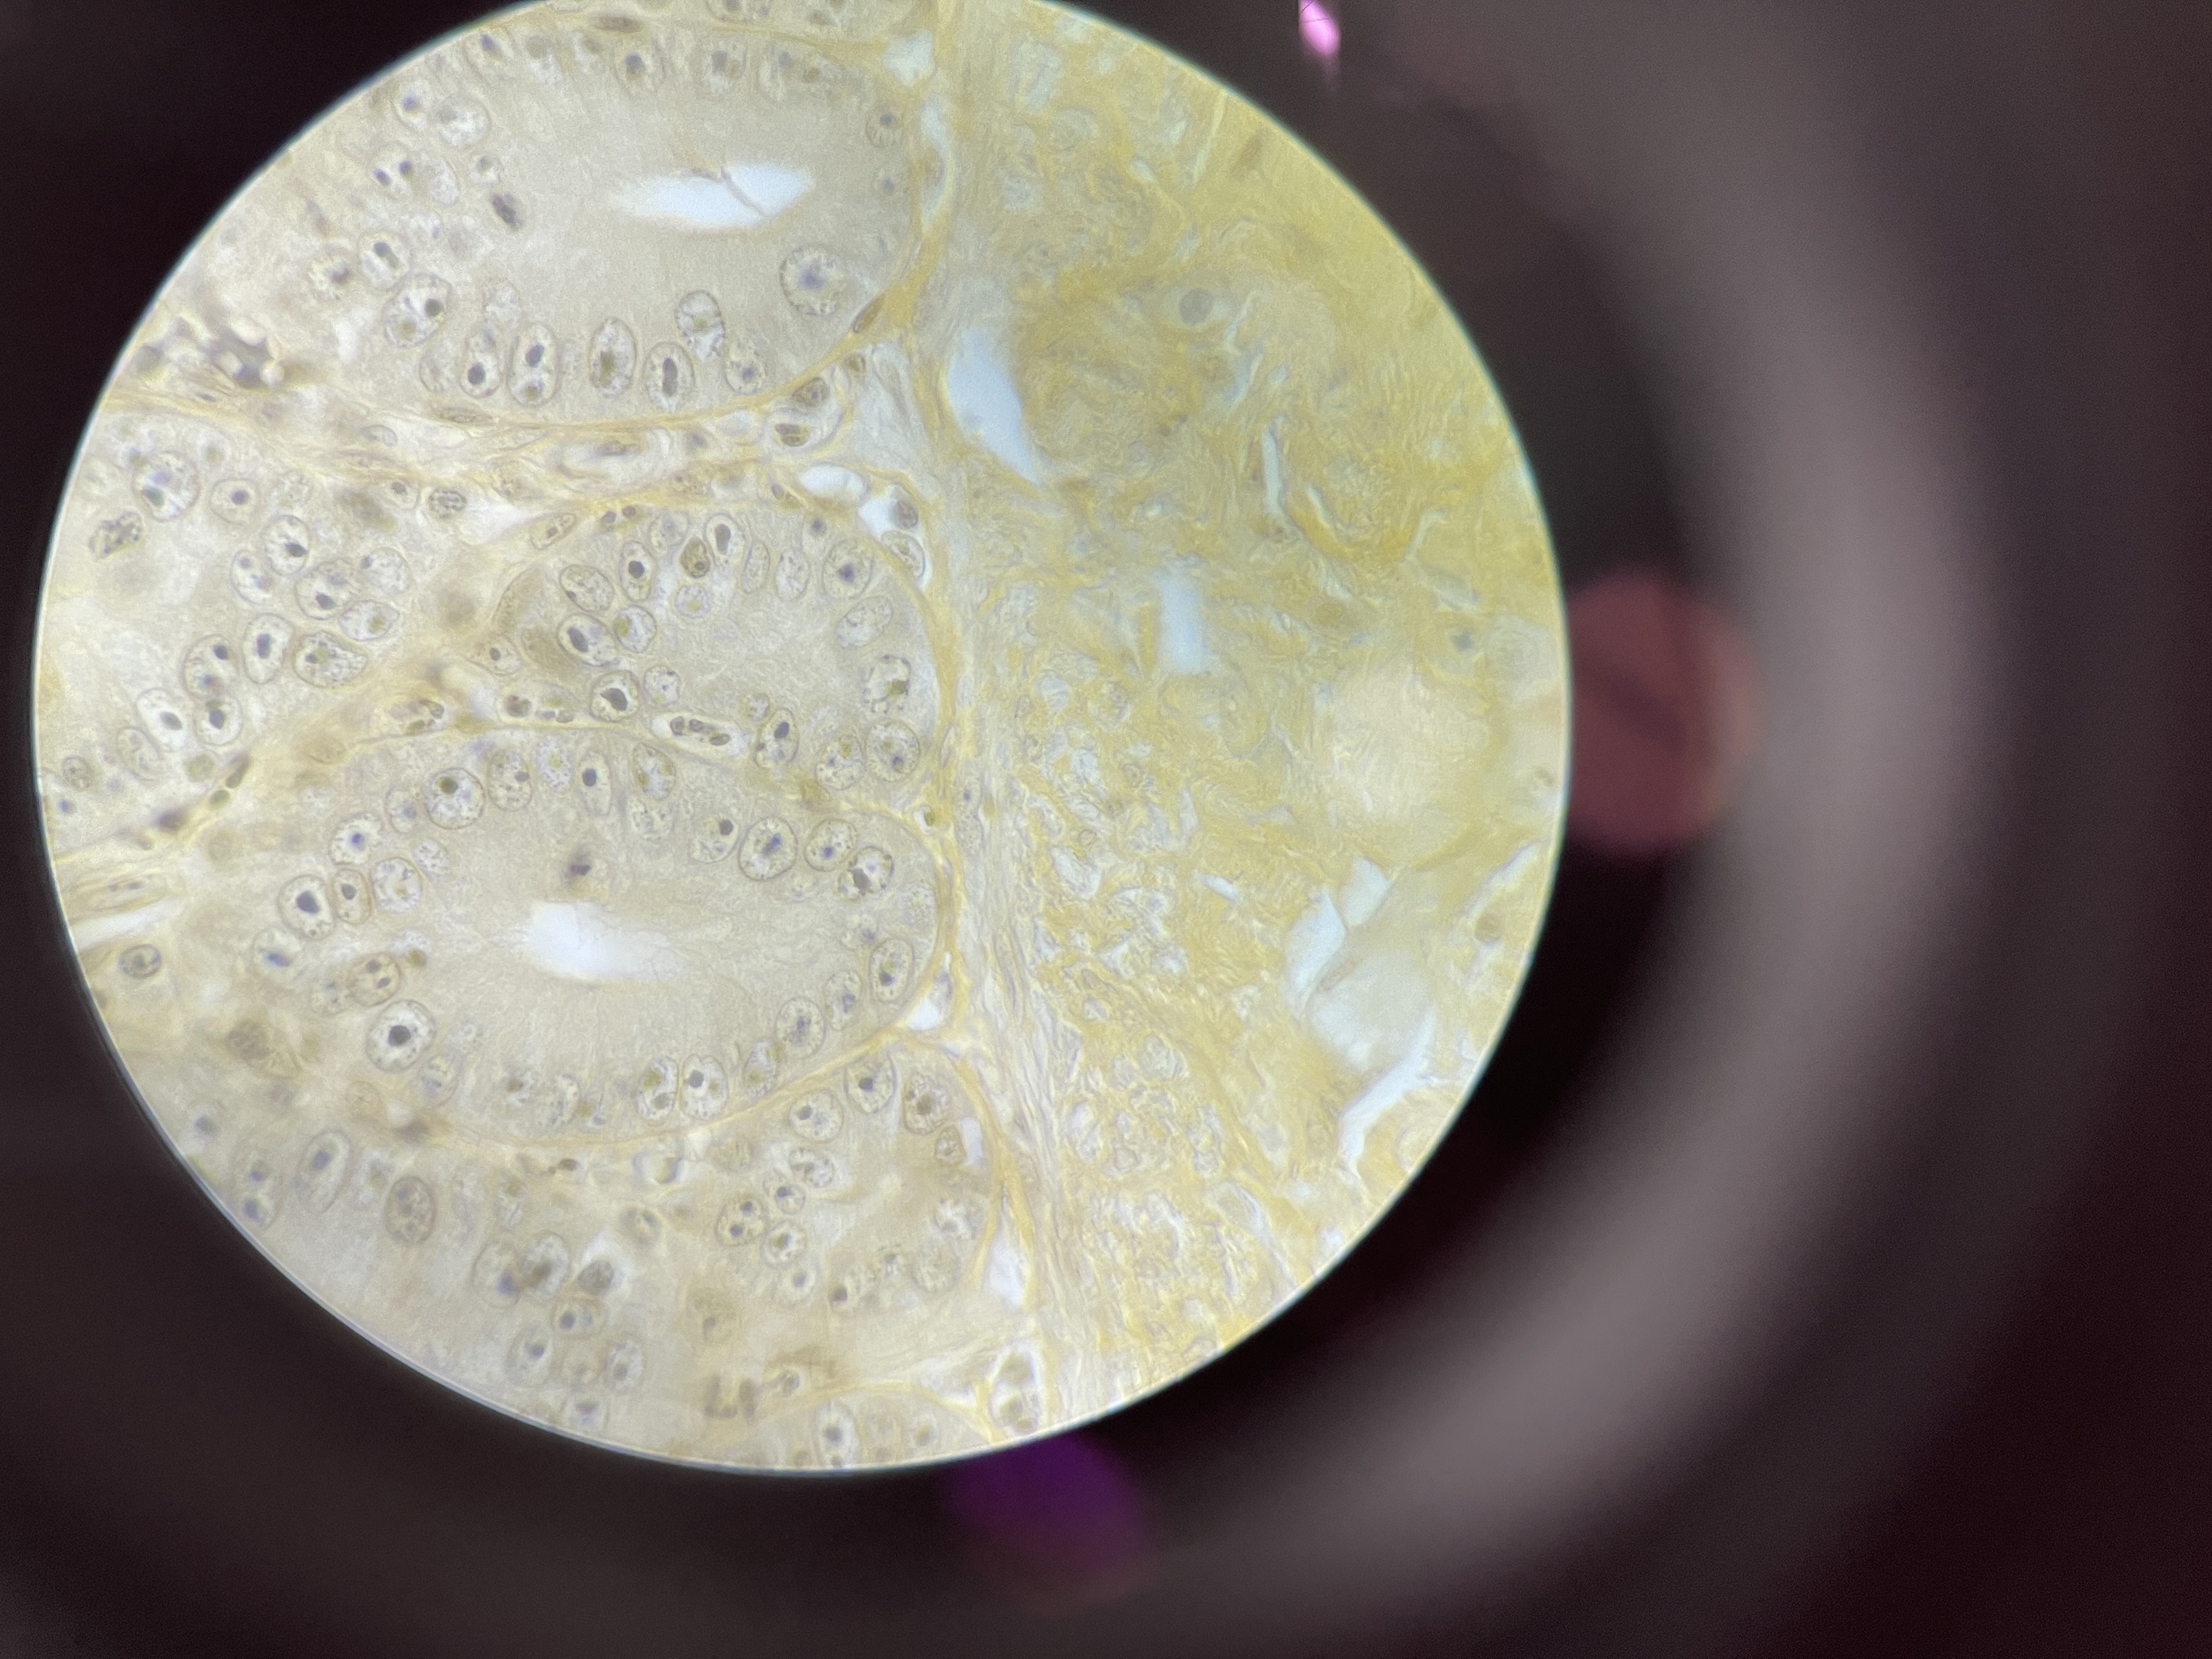

Balantidium coli

causes balantidiasis

acquired by human through pig feces

fecal, oral route

asymptomatic; diarrhea

ciliate protist